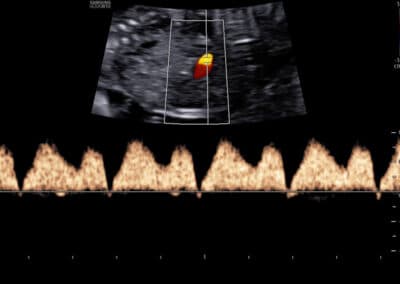

Dopplerovské vyšetření ductus venosus – normální nález (pozitivní a-vlna s PI do 1.3)

Dopplerovské vyšetření ductus venosus – abnormální nález (reverzní a-vlna s PI nad 1.3)

UZ vyšetření průtoku v ductus venosus dle FMF protokolu

Protokol pro správné Dopplerovské vyšetření průtoku krve v ductus venosus:

CRL 45-84 mm (11-13+6 týden) Vyšetření musí být provedeno během klidové fáze (absence pohybů) plodu Zvětšení (hrudník a břicho plodu vyplňují většinu obrazovky) Mid-sagitální řez tělem plodu, barevné Dopplerovské zobrazení toku krve v pupečníkové žíle, ductus venosus a v srdci Gate 0.5-1mm přes ductus venosus (místo aliasingu – světlé barvy při Dopplerovském vyšetření) Odklon průběhu v ductus venosus 0-30º od vertikální osy Nízký filtr (50-70 Hz) Vysoká rychlost posunu křivky (2-3cm/s)